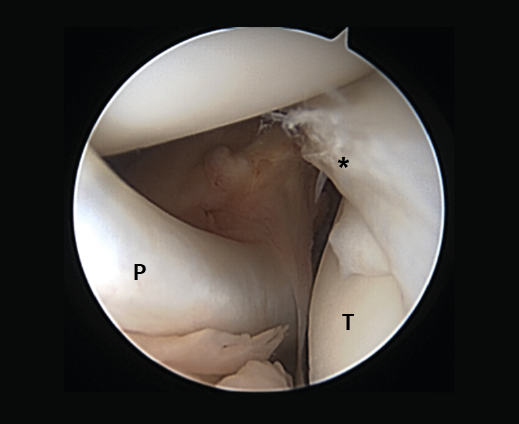

Meniscal root lesions

Meniscal root lesions are lesions located at less than 1 cm from the bone insertion of the meniscus, or lesions that involve bone avulsion of the anchoring zone (Figure 4). While lesions of the posterior root of the medial meniscus are related to degenerative processes, lesions of the posterior root of the external meniscus are associated to lesions of the ACL (7-12%)(30). Rupture of the posterior root of the medial meniscus biomechanically behaves like a total meniscectomy(31), while rupture of the posterior root of the external meniscus associated to ACL rupture results in an increase in anterior translation of the tibia and adds increased rotational instability, incrementing pivot shift(32).

Figure 4. Rupture of the posterior root of the medial meniscus. Note the lack of continuity in the posterior horn of the medial meniscus, exhibiting a space between the root and its insertion imprint in the tibia (*). Left knee; view from the anterolateral port.